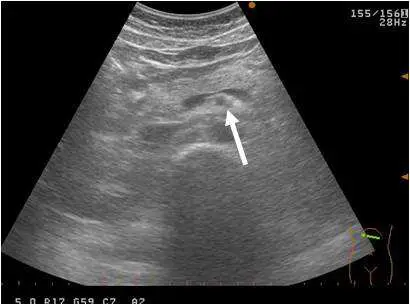

下圖為上腹部超音波影像,箭號所指的低回音圓形構造為何?

影像為上腹部超音波橫切面掃描(頻率設定 5.0 MHz),白色箭號指向影像中央偏右下方一個圓形低回音(hypoechoic)構造。該構造:

- 形態:呈圓形,邊界清晰

- 回音特性:內部為低回音至無回音,代表其內充滿血液(管腔結構)

- 位置:位於腹腔深部,胰腺體後方、腹主動脈前方,被高回音的腹膜後脂肪(retroperitoneal fat)所圍繞,形成典型的「牛眼徵(bull's eye sign)」或「靶環徵(target sign)」

- 特徵:周圍有一圈高回音脂肪環(echogenic halo),這是 SMA 在橫切面上最具特徵性的表現

此種圓形低回音結構周圍伴有高回音脂肪環的影像,是上腸繫膜動脈在橫切面超音波上的典型外觀。